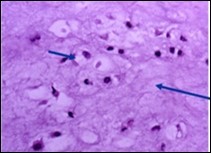

Distinction between benign cartilaginous lesions and atypical cartilaginous tumour or grade 1chondrosarcoma (ACT/CS1) can be challenging, Typically, benign cartilaginous lesions are hypo-cellular, in contrast to hyper-cellular atypical cartilaginous tumour or grade 1 chondrosarcoma 5, 6. Figure 1, Figure 2, Figure 3, Figure 4, Figure 5, Figure 6, Figure 7, Figure 8.

Figure 6.Enchondroma exemplifying lobules of hyaline cartilage composed of enlarged, vacuolated cells with uniform nuclei. Focal calcification is absent 14

Figure 7.Enchondroma enunciating lobular hyaline cartilage with constituent vacuolated chondrocytes an uniform nuclei 15.

Figure 8.Enchondroma delineating hyaline cartilaginous cells with vacuolated cytoplasm and uniform nuclei 16.